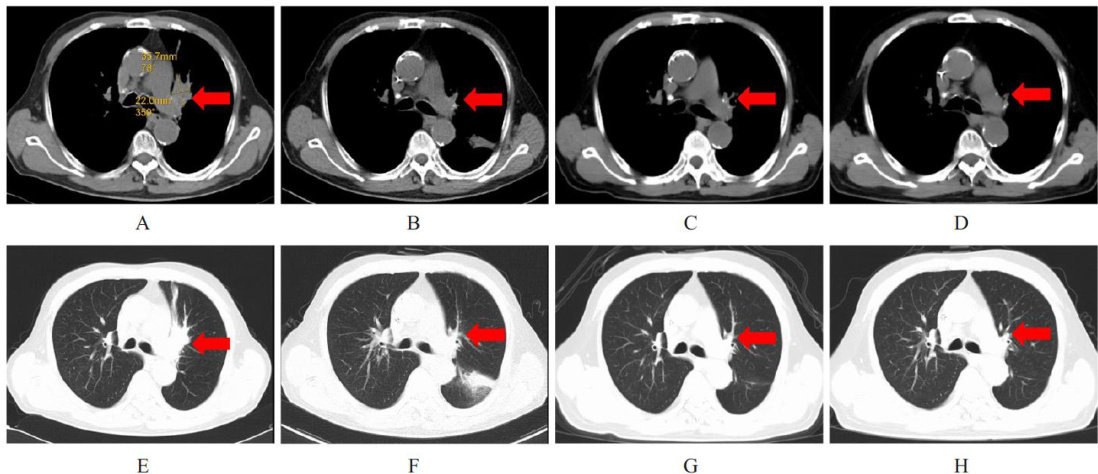

ABSTRACTLimited-stage small cell lung cancer (SCLC) is a highly malignant and rapidly progressing neuroendocrine tumor,while uremia is a complication of the end-stage of chronic renal failure. The patients with SCLC complicated with uremia have poor treatment tolerance,limited options for anti-tumor treatment regimens,and great dificulty in diagnosis and treatment. This study analyzed one case of a 69-year-old male patient with limited-stage SCLC complicated with uremia (with a history of regular hemodialysis,3 times per week),to discuss his first-line treatment regimen,eficacy,and the impact of hemodialysis on the plasma concentrations of the anti-tumor drugs,and reviewed the relevant literature to provide a reference for the treatment of similar patients. The patient was admitted to the hospital due to “cough and hemoptysis for half a month” and was diagnosed with limited-stage SCLC stage IIIA (T2aN2MO) by computed tomography (CT) and lung puncture biopsy. After discussion by the multidisciplinary treatment(MDT) team,the patient received 6 cycles of Etoposide(VP-16) + carboplatin chemotherapy combined with adebrelimab immunotherapy,follwed by sequential adebrelimab maintenance therapy. The efficacy was evaluated as partial response(PR)and the response is ongoing. During the treatment,level 4 hemoglobin decrease,level 3 neutropenia,and level 2 leukopenia occurred,which were alleviated after symptomatic treatment. The blood concentration monitoring results showed that the plasma concentrations of etoposide and carboplatin increased rapidly during drug infusion,and gradually decreased after the end of infusion.Hemodialysis could rapidly reduce the plasma concentration of carboplatin,but had no significant effect on the plasma concentration of etoposide. Therefore,the immunotherapy combined with reduced-dose chemotherapy regimen is safe and efective for this type of patient.Plasma drug concentration monitoring can be used to observe drug metabolism, but the optimal monitoring time points and clinical value need further study and validation.